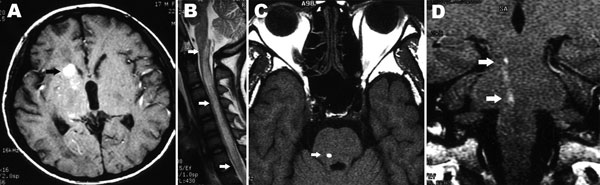

Bệnh nhân Tống T.S.,nam, 52 tuổi làm nghề thuốc bắc, vào viện với triệu chứng liệt nhẹ 2 chi dưới trong vòng 2 ngày trước khi nhập viện vì có dấu hiệu xuất huyết não không rõ nguyên nhân. Tiền sử du lịch đến nhiều quốc gia Trung Quốc, Thái Lan, Singapore, Pháp, Đức, Bỉ, Tây Ban Nha, Hà Lan và đặc biệt không có cao huyết áp. Lâm sàng không biểu hiện rối loạn ý thức, không sốt.

Các thông số cận lâm sàng không có gì đặc biệt ngoại trừ tăng chỉ số bạch cầu ái toan lên đến 22,6%, xét nghiệm dịch não tủy có giảm nhẹ đường và tăng bạch cầu ái toan 17,5% à nên được chẩn đoán sơ bộ ban đầu là bệnh do ký sinh trùng ở hệ thần kinh.

H9

Chụp MRI và CT cho hình ảnh vệt di chuyển và nhiều búi phình mạch nội sọ, chuyển bệnh nhân vào tuyến trên, xác định tác nhân qua ELISA với G. spinigerum dương tính với OD = 2,34, nồng độ IgE tăng gấp 5 lần trị số bình thường. Thuốc lựa chọn albendazol plus dexamethason], bệnh nhân hồi phục hoàn toàn sau 78 ngày điều trị.